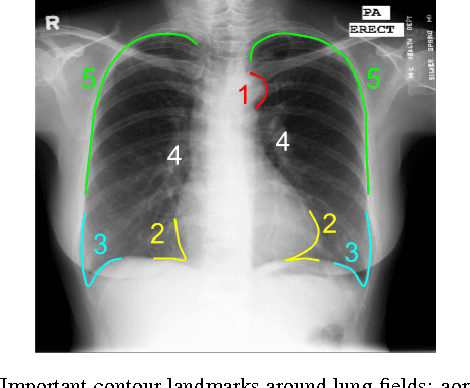

Abstract:Chest X-ray (CXR) is one of the most commonly prescribed medical imaging procedures, often with over 2-10x more scans than other imaging modalities such as MRI, CT scan, and PET scans. These voluminous CXR scans place significant workloads on radiologists and medical practitioners. Organ segmentation is a crucial step to obtain effective computer-aided detection on CXR. In this work, we propose Structure Correcting Adversarial Network (SCAN) to segment lung fields and the heart in CXR images. SCAN incorporates a critic network to impose on the convolutional segmentation network the structural regularities emerging from human physiology. During training, the critic network learns to discriminate between the ground truth organ annotations from the masks synthesized by the segmentation network. Through this adversarial process the critic network learns the higher order structures and guides the segmentation model to achieve realistic segmentation outcomes. Extensive experiments show that our method produces highly accurate and natural segmentation. Using only very limited training data available, our model reaches human-level performance without relying on any existing trained model or dataset. Our method also generalizes well to CXR images from a different patient population and disease profiles, surpassing the current state-of-the-art.